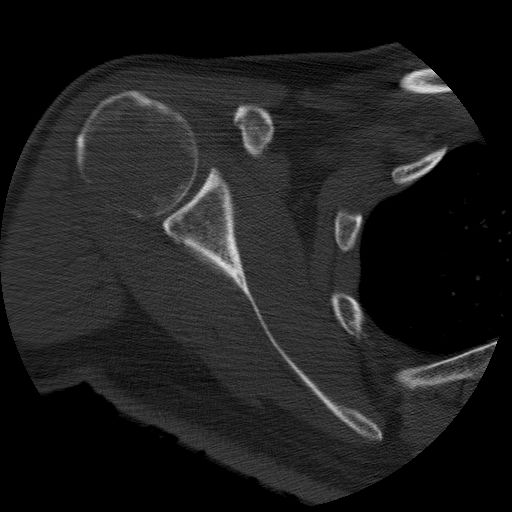

Dr. Jose Luis Molinero

Consorci Hospitalari de Vic

Home de 46 anys sense antecedents d’interès, que acut a urgències per un quadre de dolor a l’espatlla dreta de característiques mecàniques de dos mesos d’evolució, sense altra simptomatologia. Havia estat tractat ambulatòriament com una tendinitis.

Es va realitzar una placa simple de l’espatlla i donat el seu resultat un posterior TAC i PAAF.